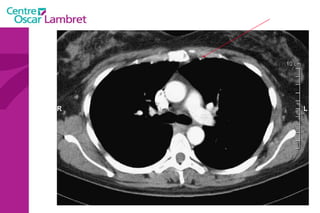

L’appareil circulatoire L’ aorte  est la plus grande artère du corps.  Elle part du ventricule gauche du coeur et apporte notamment du sang oxygéné à toutes les parties du corps via la circulation. Elle est divisée en aorte thoracique et aorte abdominale. L’aorte thoracique  comprend trois segments : l'aorte ascendante, horizontale et descendante.

L’aorte ascendante  : L’aorte ascendante constitue le segment initial de l’aorte, elle fait 27 mm de diamètre et émerge du VG, dont elle est séparée par la valve aortique. Cette portion fait 6 cm de hauteur, divisé en deux régions: le sinus de Valsalva, fortement dilaté, oblique en avant.  le grand sinus aortique, dilaté, jusqu'à la portion horizontale de l’aorte.  L’appareil circulatoire

La  crosse de l’aorte  ou aorte horizontale :  L’aorte horizontale passe ensuite derrière l’artère pulmonaire et la bronche souche gauche. Trois vaisseaux naissent de cette crosse aortique: le tronc brachio-céphalique, l’artère carotide primitive gauche, et l’artère sous-clavière gauche. Ces vaisseaux irriguent la tête et les membres supérieurs. L’appareil circulatoire

L’aorte descendante  : L’aorte descend ensuite dans le médiastin, en arrière du cœur et en avant de l’oesophage dans sa partie supérieure, en arrière dans sa partie inférieure. Cette partie est relativement fixée par rapport aux deux autres segments. La jonction entre l’aorte horizontale et descendante est appelée isthme   aortique.  Elle traverse ensuite le diaphragme et devient l’aorte abdominale. L’appareil circulatoire